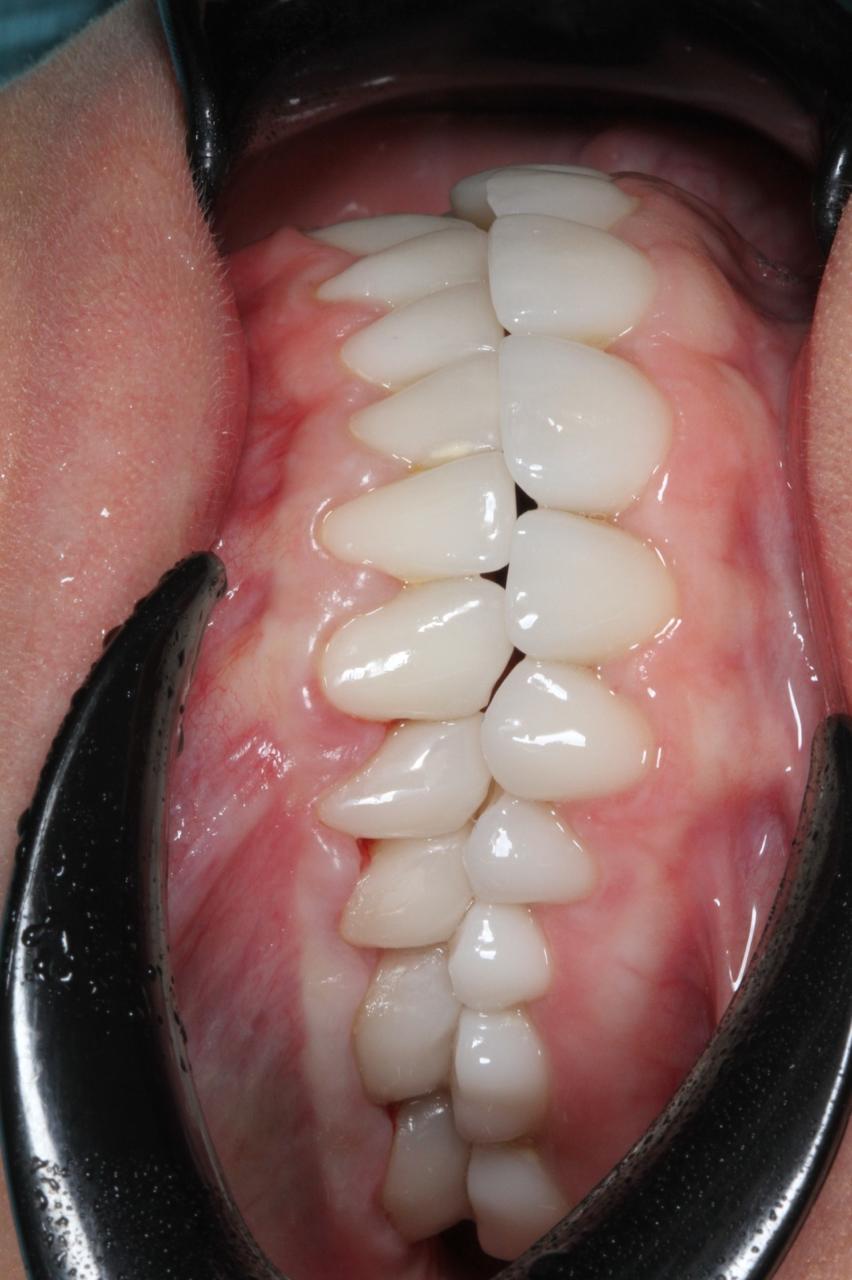

- Комплексное лечение стоматологических больных, в том числе с привлечением смежных специалистов. Функциональный анализ. Компьютерное моделирование и планированание.

- 2019г.Повышение квалификации. Курс " b.o.p.t концепция Биологически Ориентированная Техника Препарирования " под руководством Dr. Ignazio Loi

- 2008г.«Реабилитация пациентов высокоэстетичными несъемными ортопедическими конструкциями. Вкладки, накладки и виниры, изготовленные из керамики и композиционных материалов» в Стоматологическом Клиническом Учебном Центре «БиоСан»